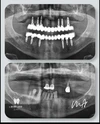

الدكتور دت. محمد أسكار طبيب أسنان

علاج الزرع

طبيب أسنان